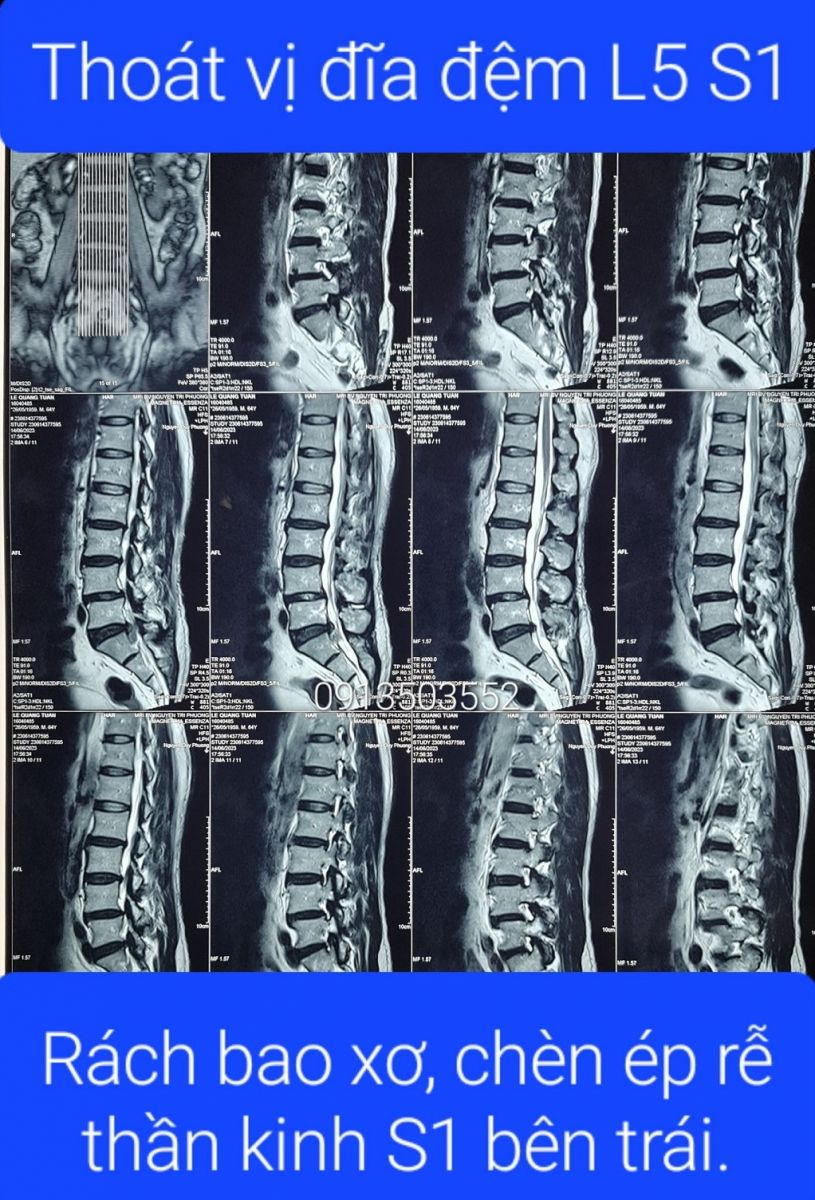

Thoát vị đĩa đệm L5 S1 Thoát vị đĩa đệm L5 S1

Thoát vị đĩa đệm L5 S1 là gì? Cách chữa như thế nào? Có chữa khỏi được không? Mời quý khách nghe và xem thực tế, bệnh án thoát vị đĩa đệm L5 S1 được quý bệnh nhân đã chữa khỏi bệnh đồng ý cho phòng khám đông y Bảo Minh chia sẻ ở đây.❮ đọc tiếp ❯